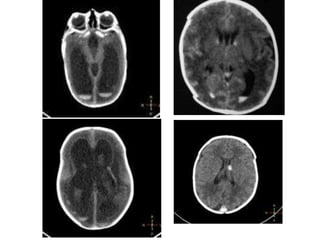

5. Diagnóstico:

RECONHECIMENTO DO RN DE RISCO ( PT <32 sem na UTI )

– USG;

• 3º dia de vida

• 7 º dia de vida

– GRADUAÇÃO DA SEVERIDADE

• Hemorragia na MG

• Hemorragia intra-ventricular sem DV

• Hemorragia intra-ventricular com DV

• Ecodensidade periventricular

Grading system Severity of GMH/1VH Description of findings

Papile I Isolated GMH (no IVH)

II IVH without ventricular dilatation

III IVH with ventricular dilatation

IV IVH with parenchymal hemorrhage